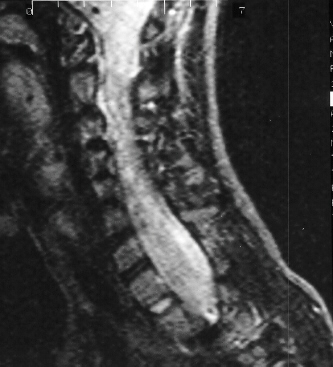

In preparation for spinal fusion for stabilization of this kyphoscoliosis

he underwent a MRI of the brain cervical and thoracic spine and CT of the

thorax. The brain and cervical spine showed no evidence of tumor. The lower

cervical and upper thoracic canal was enlarged without evidence of cord

compression, a finding consistent with dural ectasia

.

There is soft tissue protrusion into the thoracic canal that may resemble

a dumbbell lesion.